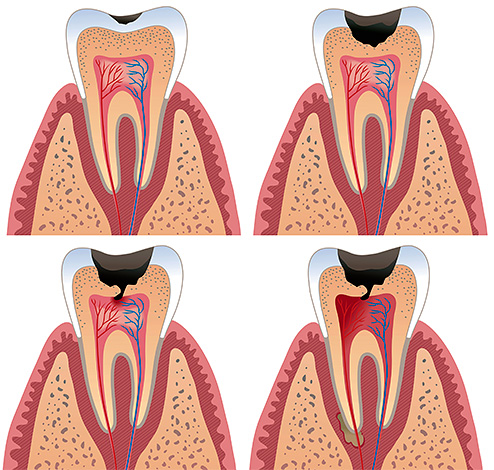

La pulite è un processo infiammatorio che si verifica nella cosiddetta camera pulpare, o, altrimenti, nel "nervo" dentale (fascio neurovascolare). E questo processo è associato nella maggior parte dei casi all'attività dei microrganismi: a seguito di carie profonde non trattate, la microflora patogena prima o poi penetra attraverso la dentina assottigliata nei tessuti molli della polpa con la comparsa di segni caratteristici di pulpite dentale.

L'infiammazione nella polpa procede secondo le stesse leggi di qualsiasi altro tessuto. Sullo sfondo degli effetti aggressivi dei batteri e delle loro tossine sui tessuti viventi, si verifica una morte graduale delle cellule, che attiva i fattori di infiammazione. Se potessimo osservare questa immagine al microscopio, il suo significato sarebbe il seguente:

- l'immunità invia cellule (leucociti) per combattere l'infezione e distruggere la fonte del danno alla polpa;

- il risultato di questa lotta sono i cambiamenti strutturali nel tessuto pulpare, fino alla sua completa necrosi (necrosi) e la comparsa di una clinica caratteristica di pulite acuta.

I tessuti molli all'interno del dente non possono riprendersi da soli, ma il processo può passare a un lungo processo cronico con un'infiammazione limitata dai tessuti circostanti - questo aiuta a proteggerli dalla fusione purulenta versata.

Nell'immagine seguente, questo processo è mostrato schematicamente: